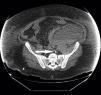

A patient underwent CRRT throw a left femoral vein catheter (34cm–13.5F). Immediately after the insertion we detected problems in the circuit blood flow and the patient deteriorated. A CT scan showed the tip of the catheter in the left lumbar vein beside a retroperitoneal haematoma (Fig. 1). Another patient (same catheter and insertion technique) showed persistent blood flow problems and in a CT scan the catheter was detected in an accessory left hemiacygos vein and already visible in the plain abdominal X-ray (Fig. 2). Because presumably an eco-directed insertion would not have prevented these anomalous locations, in the event of serious flow problems, a radiologic exploration can help ruling out this unusual and scarcely reported malposition that demands immediate withdrawal of the catheter.